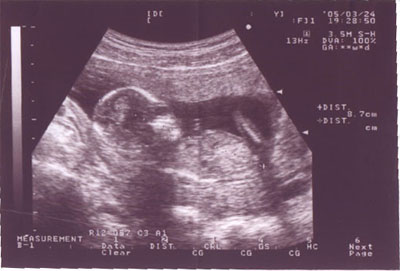

▲每次去產檢都會得到醫生送的超音波照片,沒有想像力的話真的很難看懂,左邊圓圓的是頭,腳在右邊